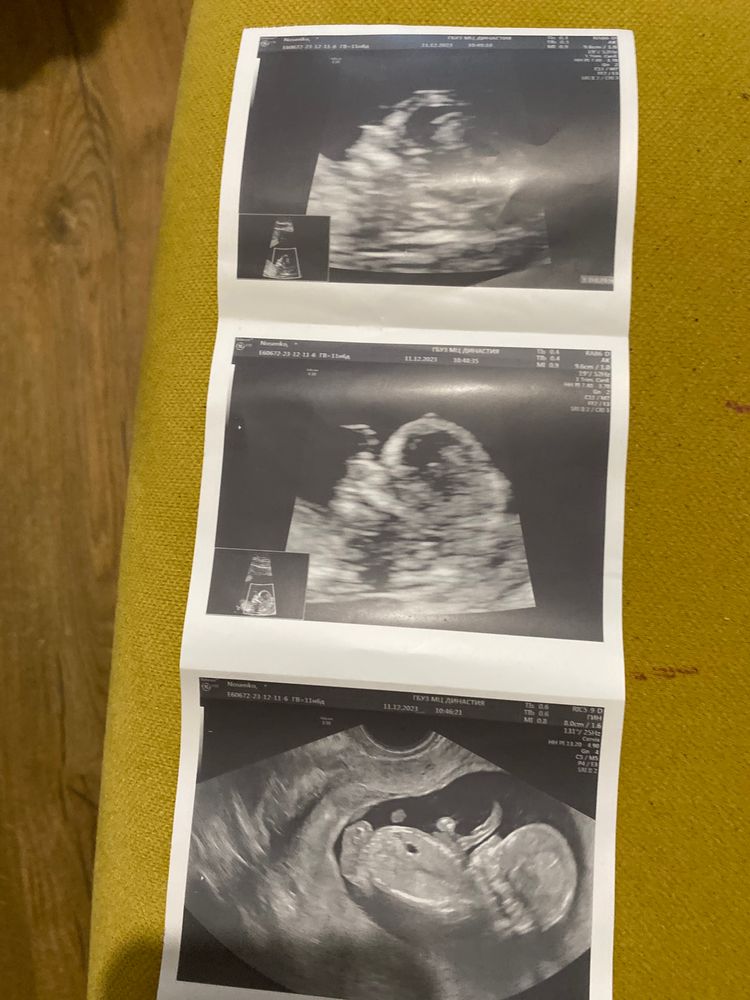

Пол малыша

Я тоже не совсем понимаю, но похоже пацан…. А врач узи что сказал? Наш сегодня четко показал писюн😁 срок по мес. 10,2, а по узи 10.5 поставили

По фото не совсем понятно, но я ближе к мальчику склоняюсь. По наблюдениям, как правило мальчишки бегут вперед в размерах, девчонки намного реже

По этим фото не понятно.

Нет нужного ракурса

Юлия *, верхнее не то? Изображение

tata, посмотрите рядом маленькое окошечко, область увеличения. Это голова